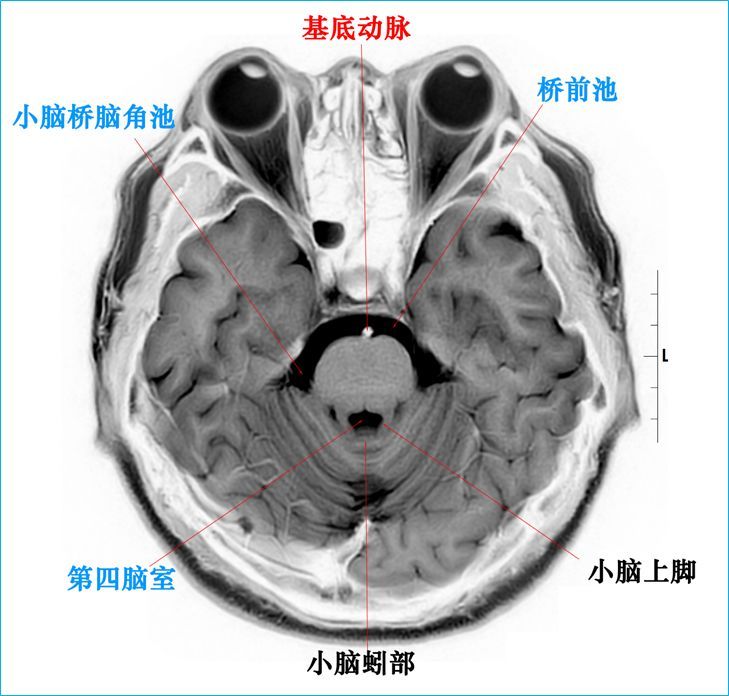

T2WI反相图学下的颅脑断层解剖(吴老师亲自手动标准)以及标本断层解剖,满满干货,坐在小板凳上,一起学习吧...如有标注错误,望大家多多批评指正。MR图像全部来自黄山昌仁医院的3.0TMRI。

3.0T-T2WI反相图学颅脑断层解剖